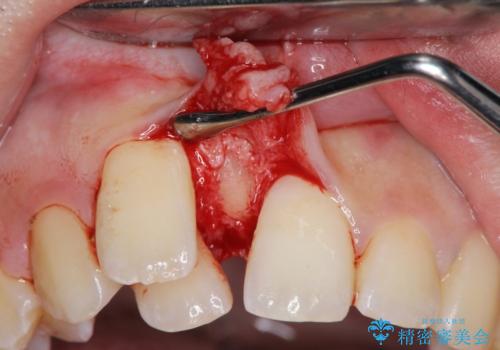

正中過剰埋伏歯で生じた前歯の審美障害 矯正治療での改善

- 前歯の見た目に悩まれて来院されました。

当初他院では、抜歯を行いセラミックブリッジを提案されていましたが、他の方法はないかと総合歯科治療を行う当院へと相談来院されました。

「時間がかかっても良いので、できれば歯を抜かずに矯正治療で治したい。」という強い希望があったので、矯正治療で歯並び・審美性の改善を計画します。